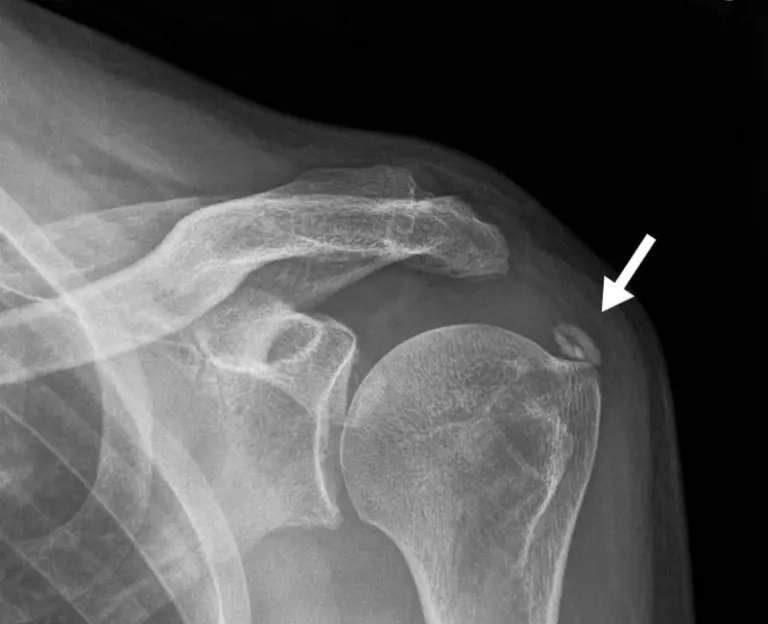

인대에 칼슘이 쌓이는 석회화 건염(Calcific Tendinitis)과 관절강 내에 칼슘이 쌓이는 가성통풍(Pseudogout)은 40∼50대부터 잘생긴다(가성통풍은 통풍과 유사하게 관절염의 원인이 되지만, 관절에 요산이 쌓여 생기는 통풍과 달리 가성통풍은 관절에 칼슘 결정들이 쌓여 생긴다). 오랫동안 사용해 온 관절과 인대의 탄력이 떨어지면서 방어 기전의 하나로 칼슘이 모이는 것으로 추정된다. 엉덩이나 무릎ㆍ어깨관절이 끊어질 것 같은 극심한 통증을 초래한다. 뇌의 기저핵이 아닌 소뇌나 측두엽 등에 석회질이 생기면 간질이나 심각한 인지기능 장애를 일으킬 수 있으므로 정확한 검사가 필요하다.

미네랄_칼슘_석회화_골다공증.jpg 석회화는 칼슘이 과도하게 침착돼 몸의 조직이나 기관이 돌처럼 단단해지는 것이다. [이미지 출처: 구글]